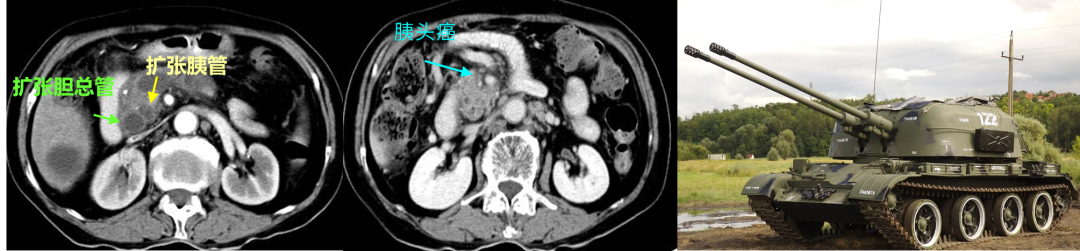

14.假包膜征

腺泡细胞癌、实性浆液性囊腺瘤(SCN)、肝样腺癌。

图16 假包膜征

(图片来源:余日胜教授讲课使用)